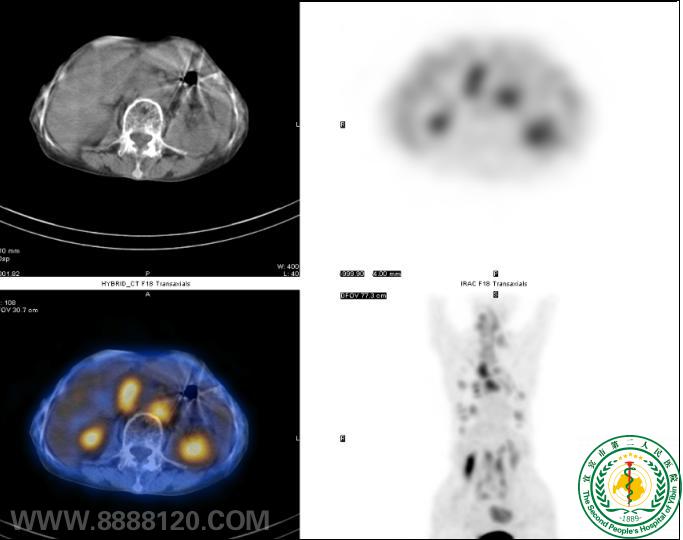

“鹰眼PET/CT”发现结肠Ca术后多处转移一例

“鹰眼PET/CT”发现结肠Ca术后多处转移一例6507